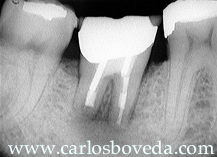

El paciente L.L. regresa de consulta con el protesista luego de habérsele reconstruido nuevamente el segundo molar inferior derecho, diente en el cual nosotros realizamos un nuevo tratamiento de conductos dos semanas atrás. El paciente se presenta totalmente asintomático, habiendo desaparecido la fístula inicial y presentando la siguiente imagen radiográfica :

(Haga click en la imagen para agrandar)

Esta imagen radiográfica se corresponde con el postoperatorio inmediato de la cirugía. Notese en este momento la ausencia de sobre obturaciones y de como la sobresaturación general del caso era significativamente mayor a lo que se podía estimar en la radiografía preoperatoria luego del retratamiento endodóntico de este segundo molar. (Haga click en la imagen para agrandar)